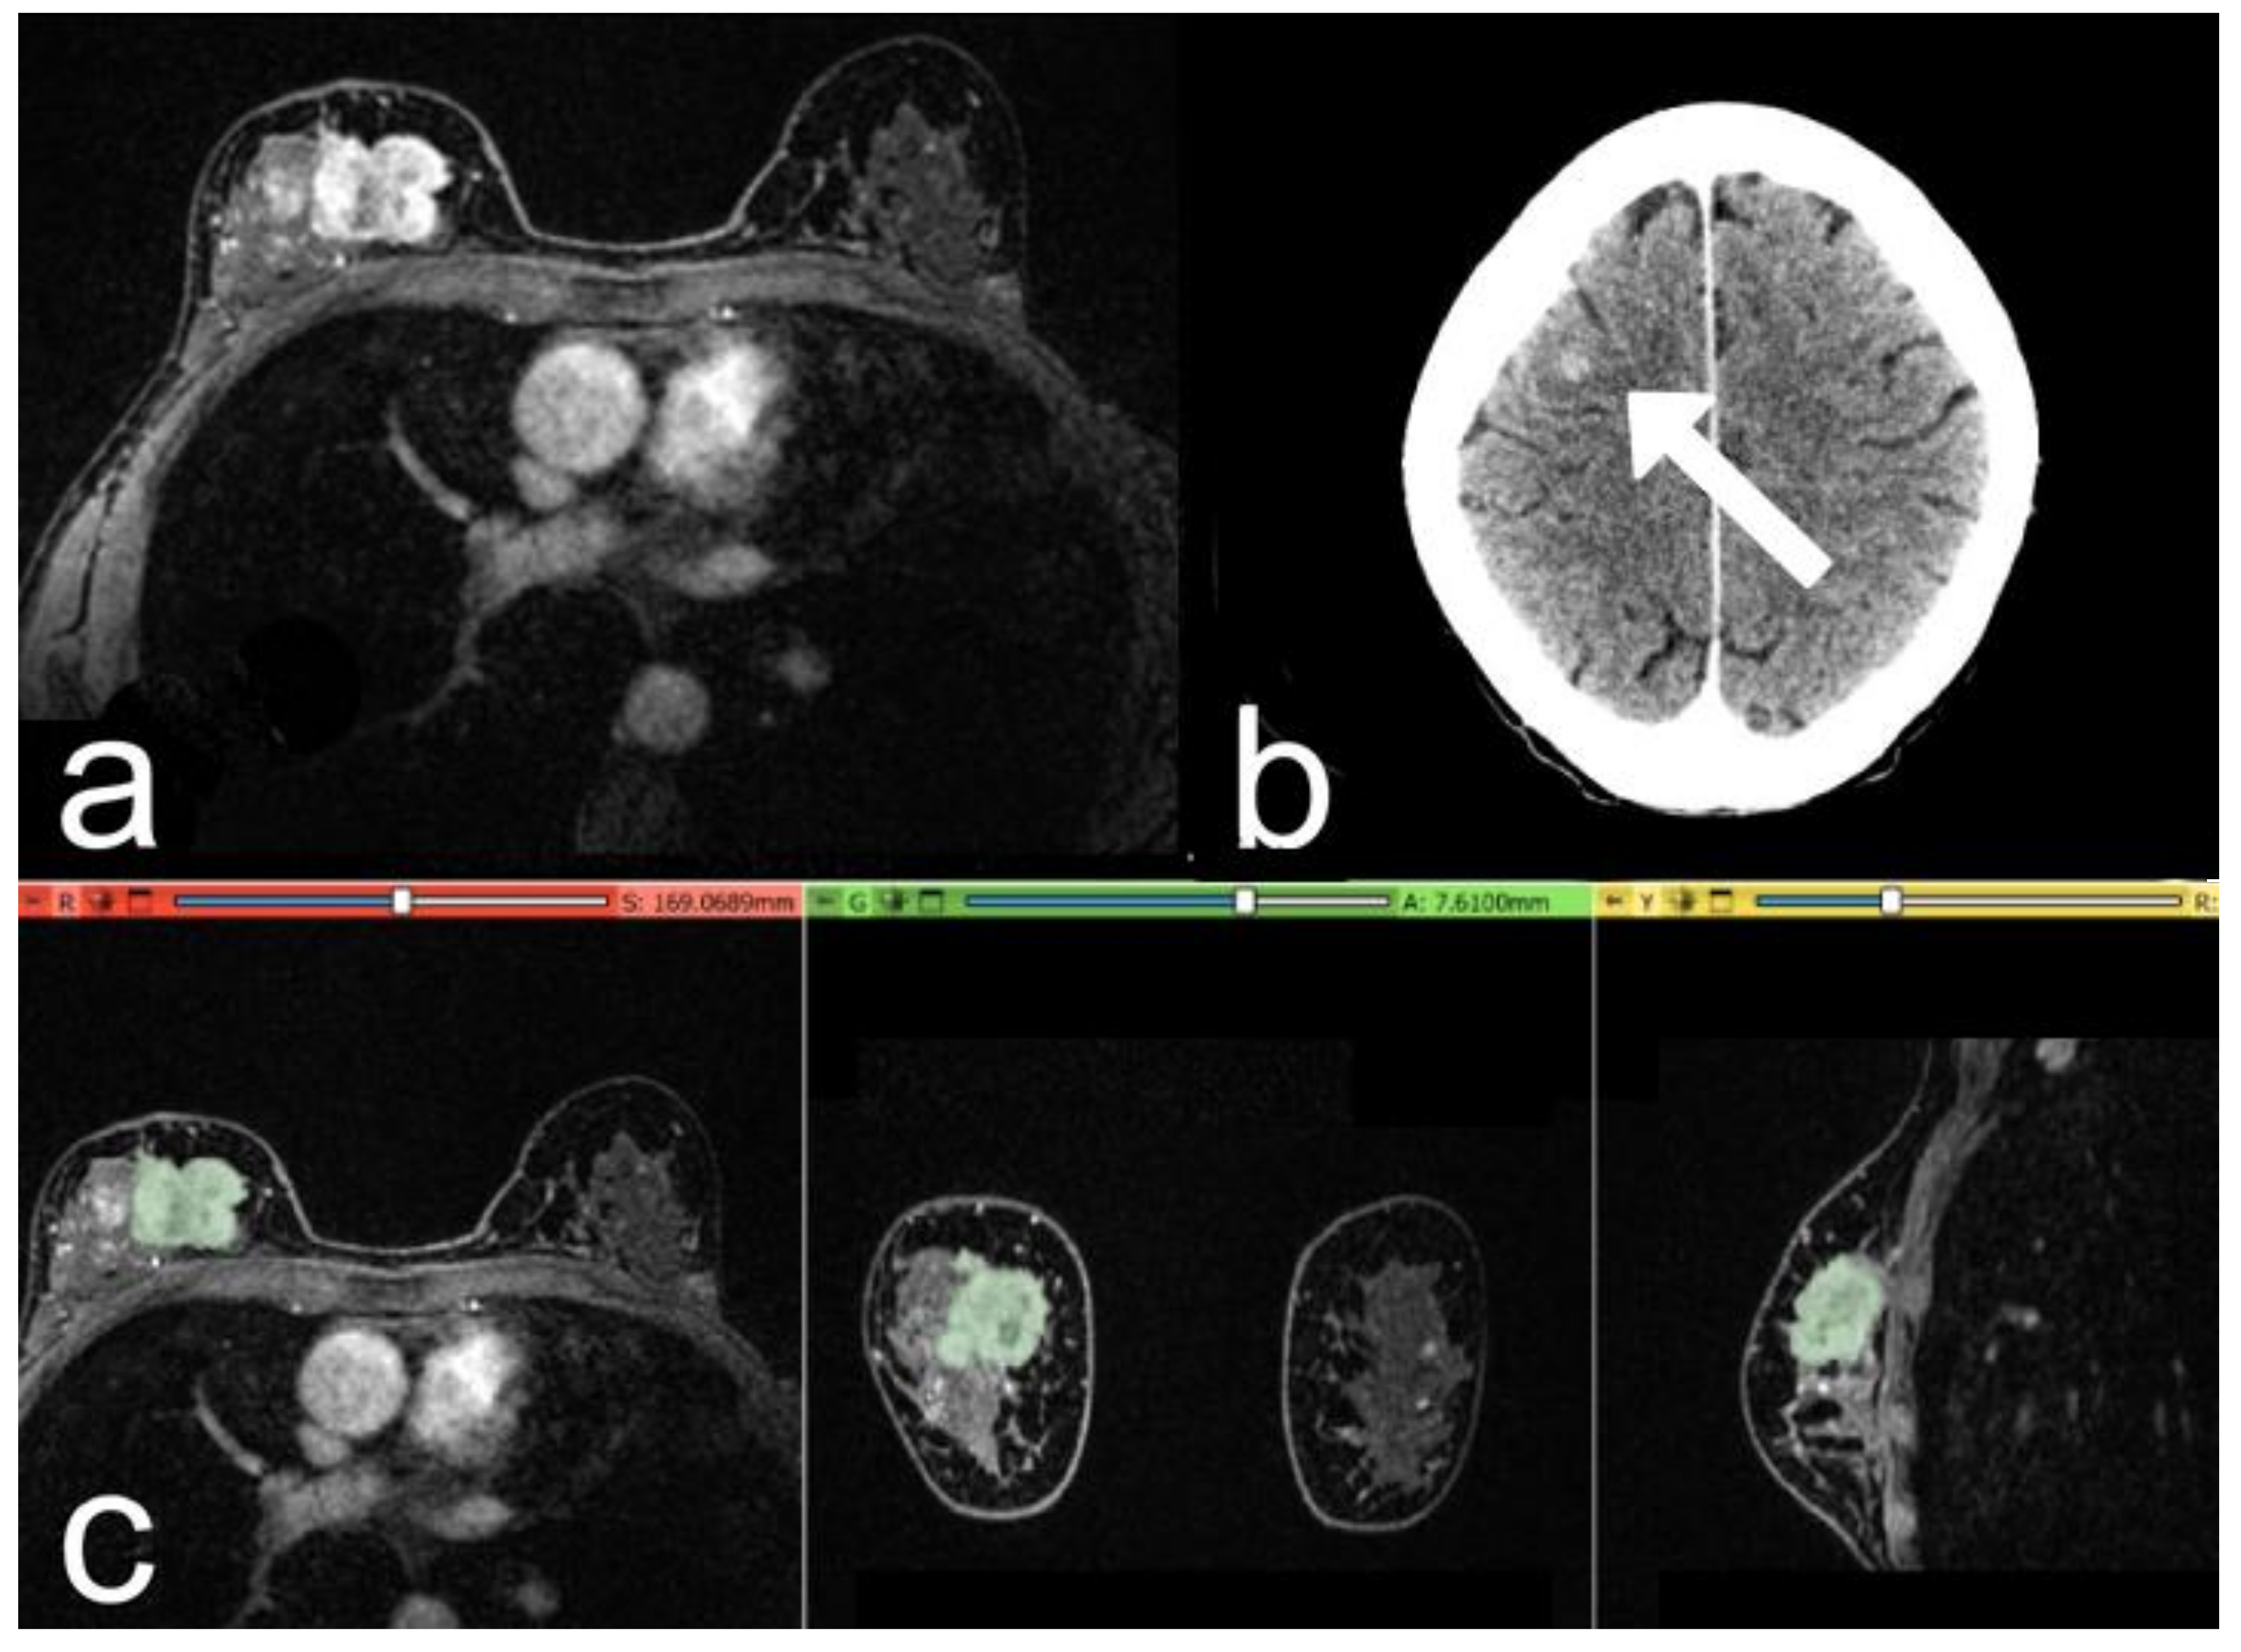

Simple Summary

2. Materials and Methods

2.4. Segmentation and Pre-Processing

2.5. Volumes Extraction